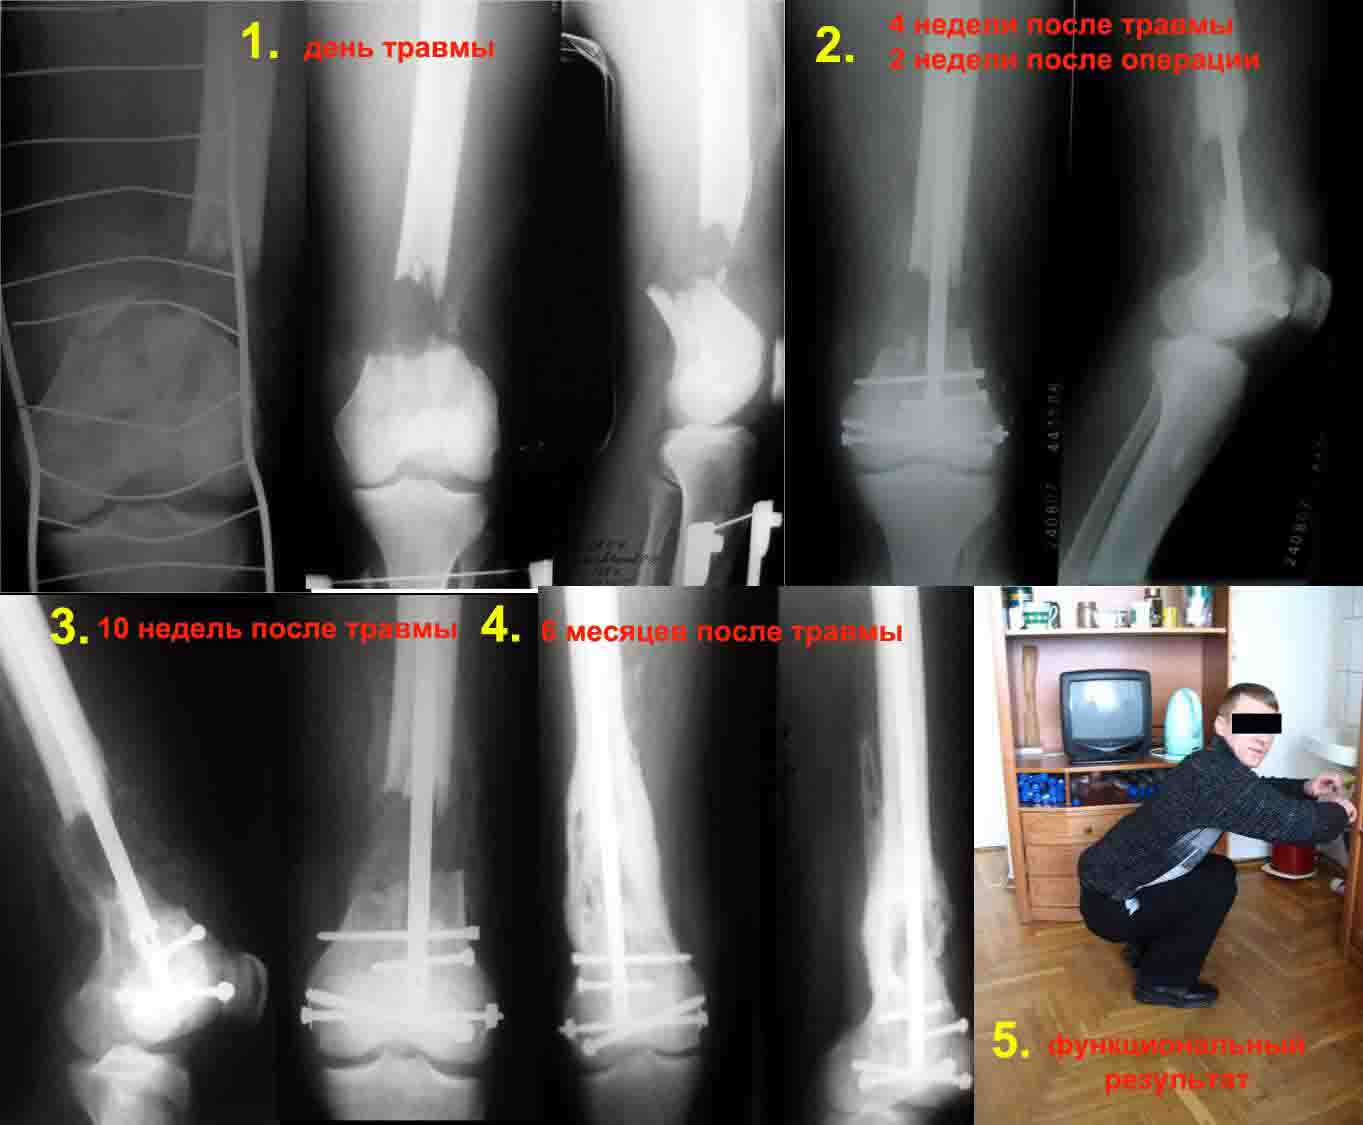

Для примера вложенный файл.

1. Открытый с дефектом кости 5 см оскольчатый внутрисуставной перелом дистального эпиметафиза бедренной кости. Величина дефекта установлена после сравнительных рентгенограмм обоих бёдер с линейкой. При поступлении выполнена ПХО раны, скелетное вытяжение за бугристость большеберцовой кости.

2. После долгих сомнений выполнена открытая репозиция перелома эпифиза бедренной кости, закрытый блокированный интрамедуллярный остеосинтез (к слову, оперативное вмешательство выполнено без применения ЭОПа). Предполагалась через 8 недель пластика костного дефекта спонгиозным аутотрансплантатом.

3. Снимок через 10 недель после операции. Имеется облаковидный регенерат. Решено от костной пластики воздержаться.

4. Через 6 месяцев имеем сросшийся перелом.

Безусловно, так бывает не всегда. Но, что касается показаний к костной пластике, такой вариант развития событий надо иметь ввиду.